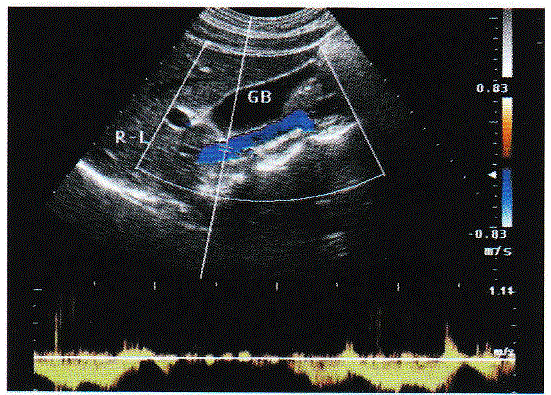

问题 请回答下图箭头所指部位及彩图取样门宽所采及部位的解剖名称:

选项 A.门静脉 B.下腔静脉 C.腹主动脉 D.肝静脉

答案 B